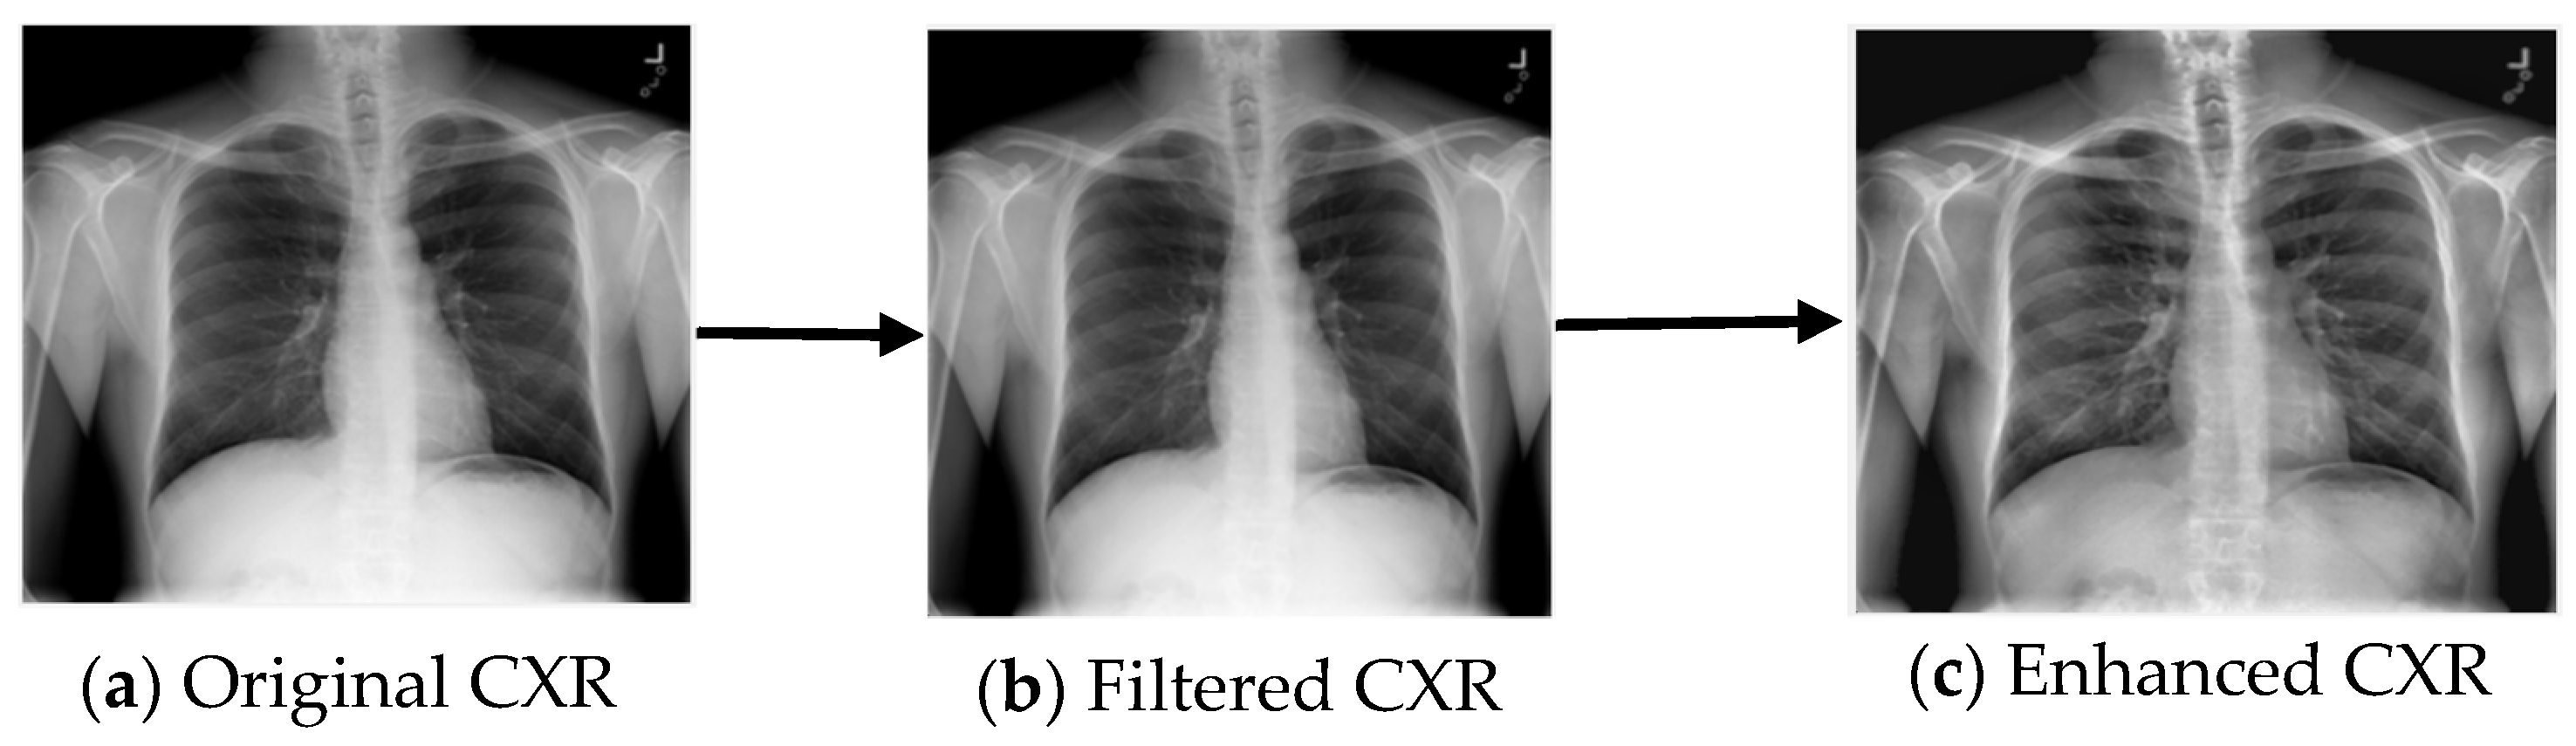

3.1. Image Preprocessing

- Rahman, T.; Khandakar, A.; Qiblawey, Y.; Tahir, A.; Kiranyaz, S.; Kashem, S.B.A.; Islam, M.T.; Al Maadeed, S.; Zughaier, S.M.; Khan, M.S.; et al. Exploring the effect of image enhancement techniques on COVID-19 detection using chest X-ray images. Comput. Biol. Med. 2021, 132, 104319. [Google Scholar] [CrossRef]

- Huang, T.; Yang, G.; Tang, G. A fast two-dimensional median filtering algorithm. IEEE Trans. Acoust. Speech Signal Process. 1979, 27, 13–18. [Google Scholar] [CrossRef] [Green Version]

- Zuiderveld, K. Contrast limited adaptive histogram equalization. In Graphics Gems IV; Academic Press Professional, Inc.: Cambridge, MA, USA, 1994; pp. 474–485. [Google Scholar]